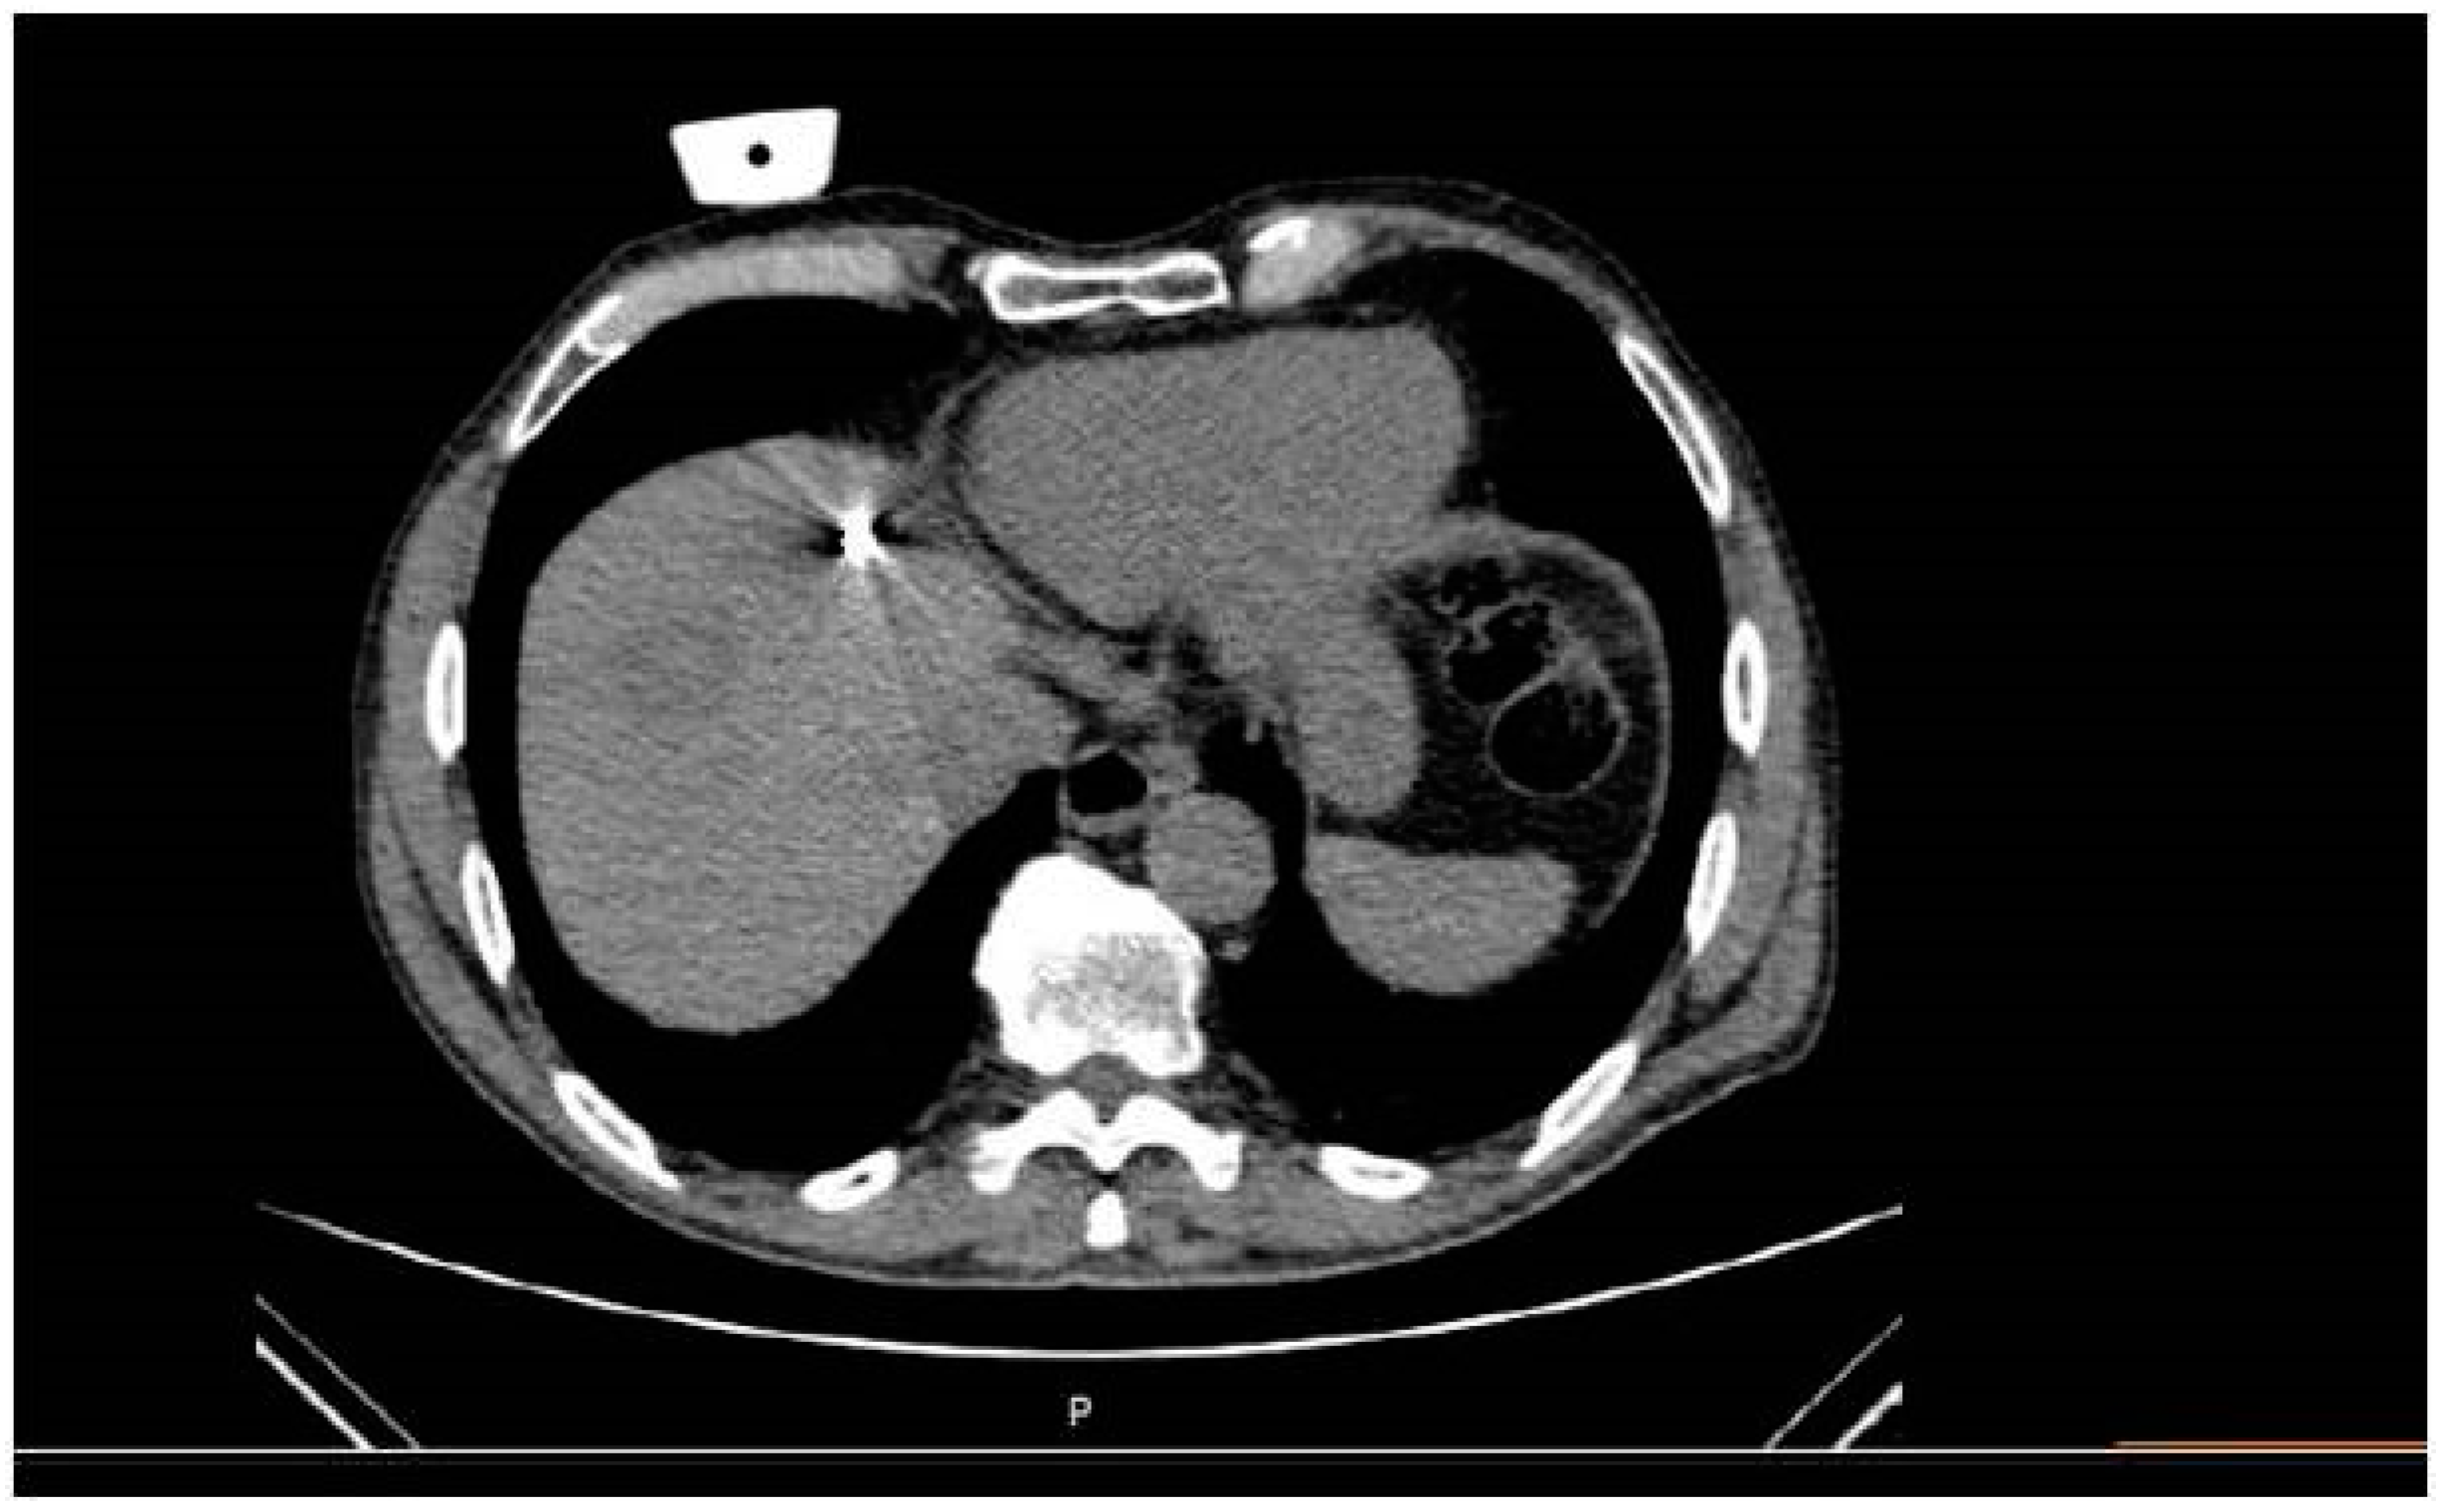

The mean total duration of the procedure from entrance to exit of the patient was 49.45 (SD = 7.53 min). Specifically, a median of 7 min was necessary for planning time and 12 min for insertion time. Whenever deemed necessary (4/16 sessions), the microwave antenna was re-positioned and a second ablation session was performed, so as to ensure that the final ablation completely encompassed both the target tumor and an annular safety zone around it that was a minimum of 5 mm thick. Navigation was used for all four repositioning. A median of 11 scans was performed including planning and control scans as well as a scan during ablation (Figure 3) and immediate imaging follow-up with 3 scans (prior to and post contrast medium injection in the arterial and portal venous phases).

On a per lesion basis, tumor remnant was noticed at one month follow-up in a single metastatic lesion (from myeloid carcinoma of the thyroid gland) (1/16, primary technical success 93.75%). This lesion was re-treated with an ablation session and no tumor remnant was depicted in the subsequent imaging follow-up (secondary technical success 100%). On a per patient basis, no disease progression was depicted in or outside the liver. Grade I self-limited complications (according to the CIRSE classification system) included small pleural effusion (n = 1) and active extravasation post antenna removal (n = 1) requiring nothing but observation. In all cases, both imaging and clinical control was performed in the first 24 h confirming the lack of a need for any further actions.

Figure 3. Same patient as in Figure 1 and Figure 2: Computed tomography axial scan during evaluation of the placement of the antenna in the target lesion and potential gas bubbles dispersion.